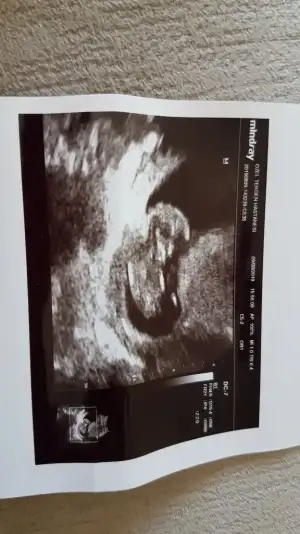

bu 12 haftalıkken

11 yada 12 hafta olmalı nub için kafa şekli erkek gibi ama tutmayabilir siz 11 yada 12 hafta usg paylaşın